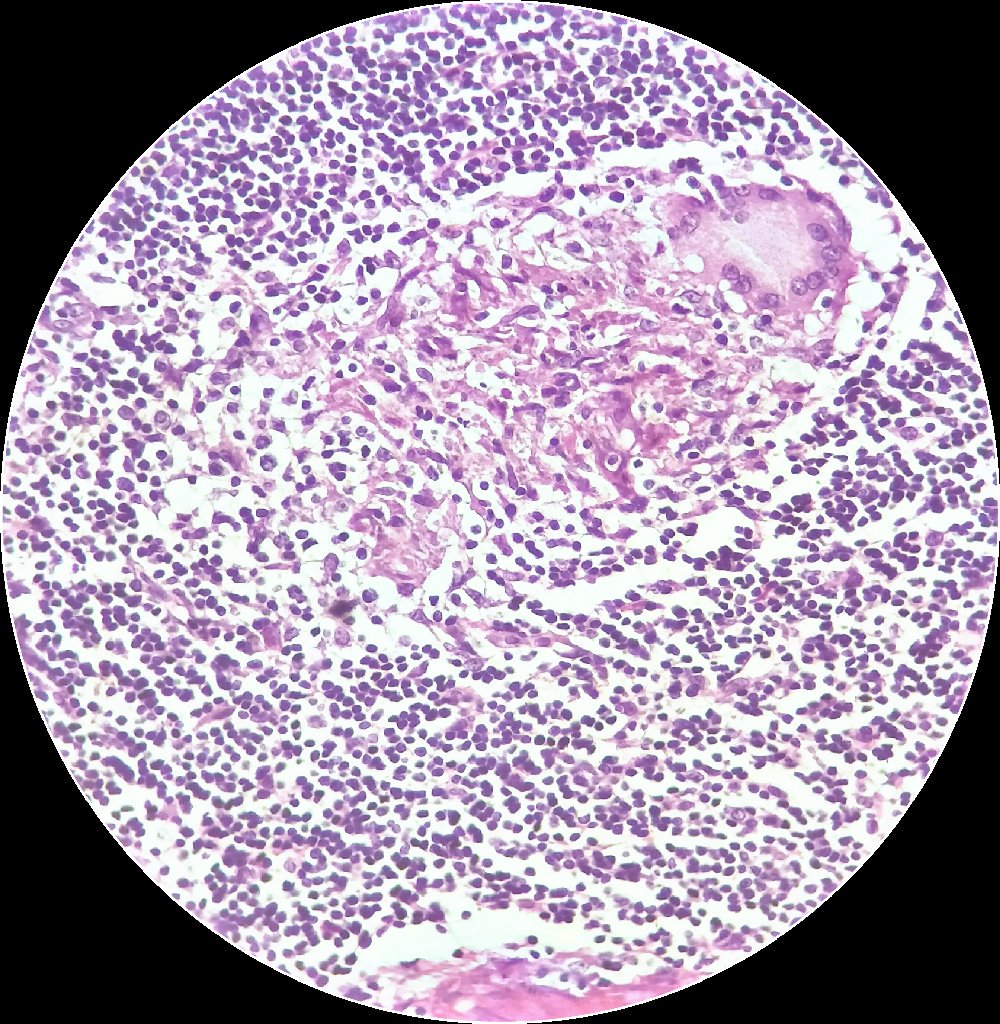

Granulomas on cytology (lymph node sarcoid)

#pathology#granuloma#PulmPath#hemepath@pathobotpic.twitter.com/tmuo8iia1b